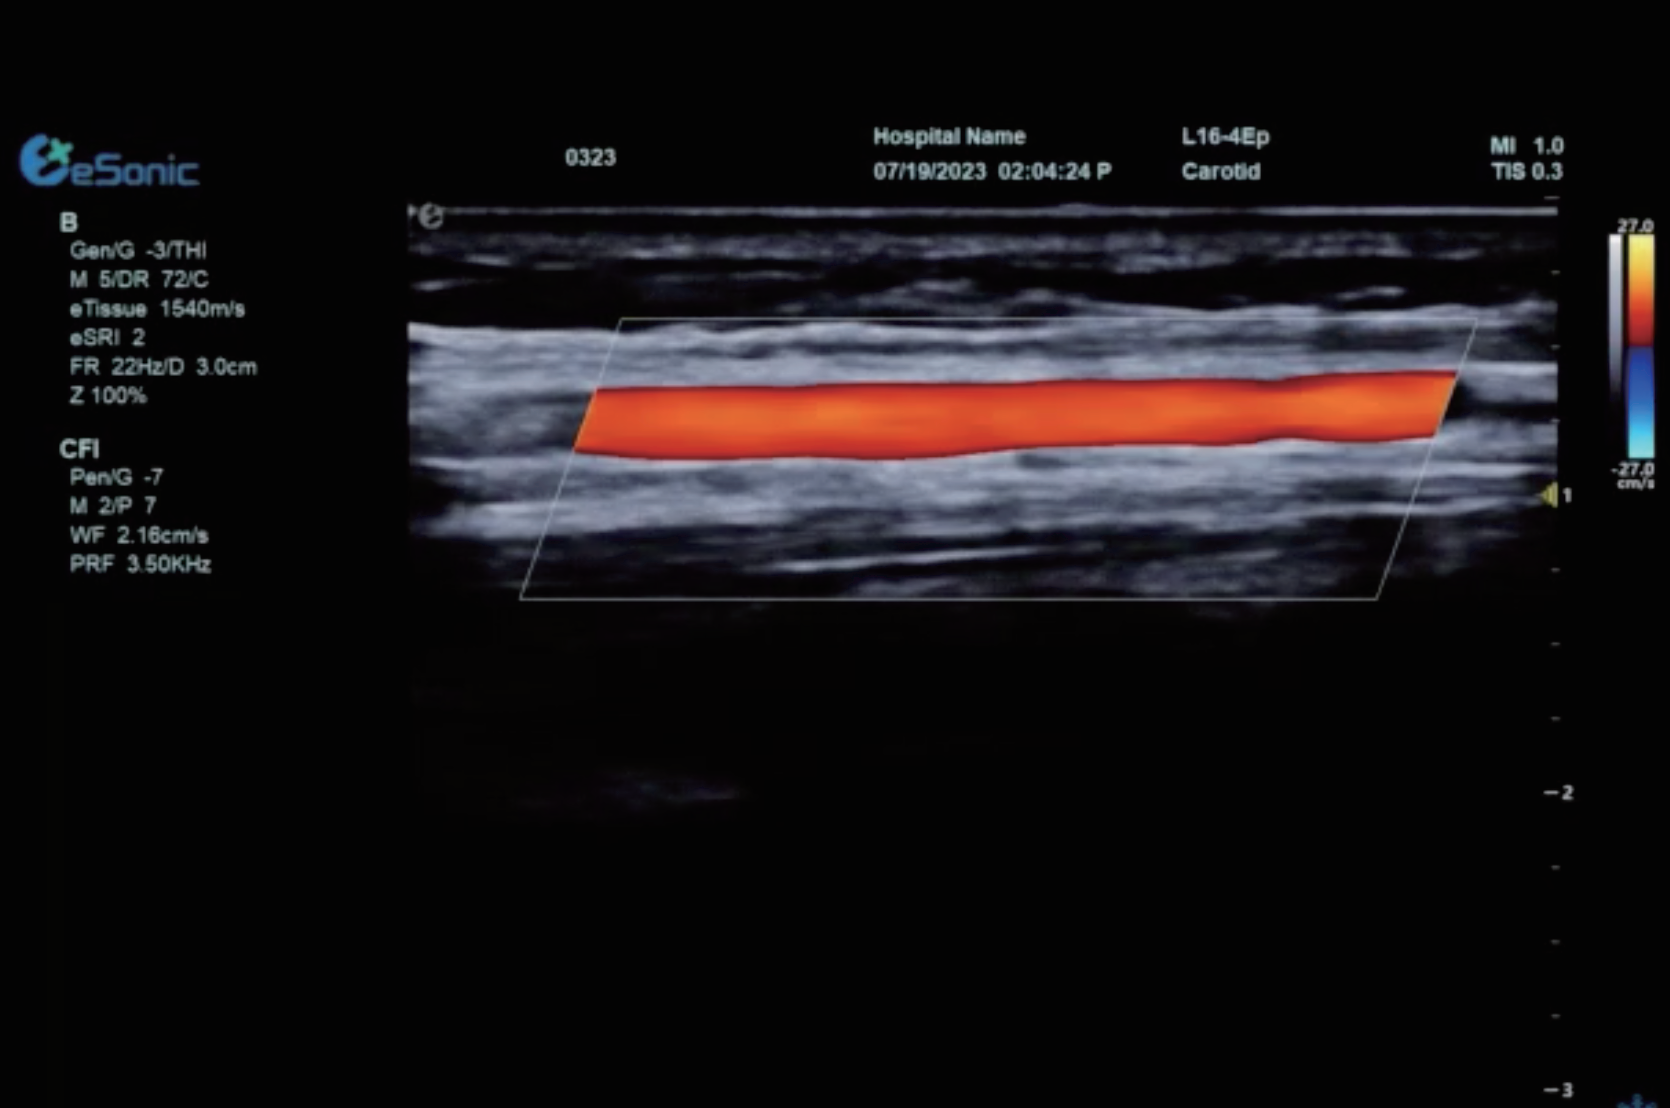

平面波超微细血流显像

彩色多普勒成像、3D壁滤波原理

血流敏感度明显提升,分辨率达微米级别

支持灰阶和微血流量同步测量、可测极低速血流的速度

多种模式,多数据定量评估。